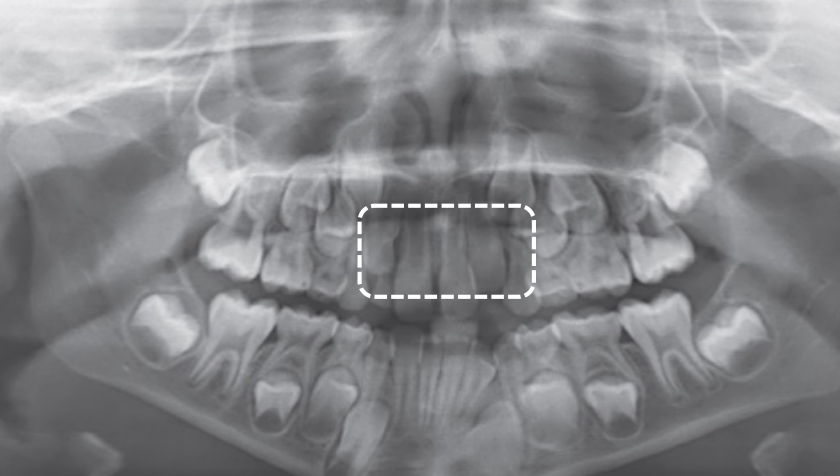

The age in this picture is characterized by the teeth erupted which are: Maxilla ABCDE and Mandible ABCDE. The teeth unerupted are the Maxilla 1234567 and the Second molar in the Maxilla- 1/3 Crown completed, Mandible- 1/3 crown completed

The age in this picture can be estimated by the erupted teeth which are: Maxilla ABCDE, Mandible ABCDE. The unerupted teeth are the Maxilla 1234567 and, Mandible 1234567 and the main identifying feature is the Second molar – Maxilla- 2/3 Crown completed, Mandible- 2/3 crown completed

At age 6 is characterized by the erupted first molar in the maxilla, and the erupted central incisor and first molar in the mandible. Teeth erupted – Maxilla ABCDE6, Mandible 1BCDE6 - Teeth unerupted – Maxilla 123457, Mandible 23457

Dental age 7 is characterized eruption of permanent teeth Mandibular Lateral Incisor, Maxillary Central Incisor

Dental age 8 is characterized by eruption of the maxillary lateral incisors

Teeth erupted – Maxilla 12CDE6, Mandible 12CDE6

Teeth unerupted – Maxilla 3457, Mandible 3457